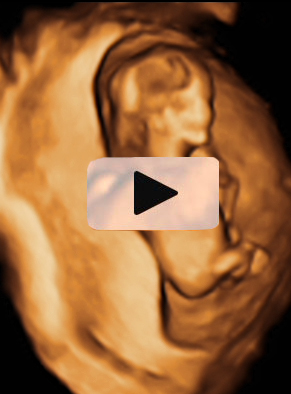

Ecografía 4D de feto de 12 semanas de espaldas

La curiosa ecografía de este feto de 12 semanas comienza con la imagen de espaldas. El niño se gira hasta colocarse de perfil y es entonces cuando empieza a mover brazos y piernas con agilidad. Todo un signo de bienestar fetal.